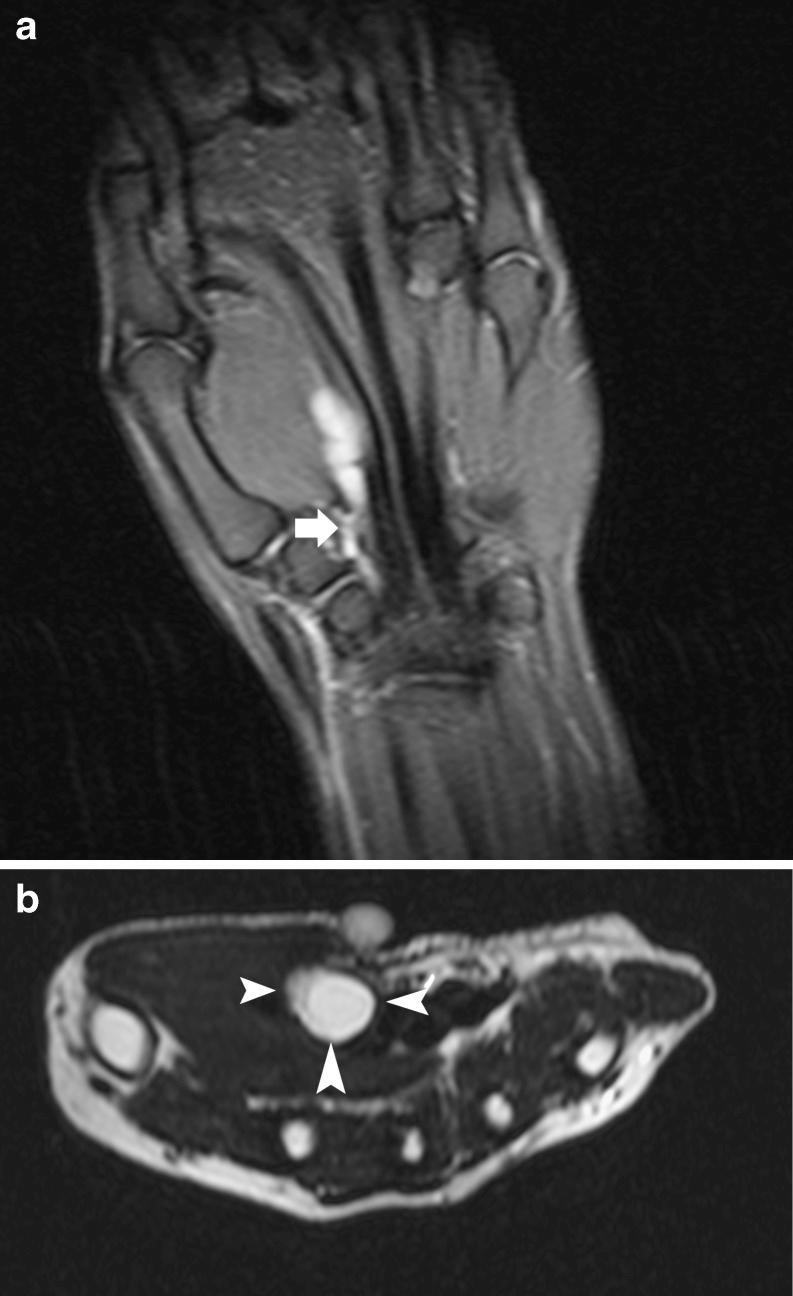

手部和腕部的假瘤性软组织病变:影像学综述

Pseudotumoural soft tissue lesions of the hand and wrist: a pictorial review.

Mimickers of soft tissue tumours in the hand and wrist are more frequent than true neoplastic lesions. Pseudotumours belong to a large and heterogeneous group of disorders, varying from normal anatomical variants, cystic lesions, post-traumatic lesions, skin lesions, inflammatory and infectious lesions, non-neoplastic vascular lesions, metabolic disorders (crystal deposition disease and amyloidosis) and miscellaneous disorders. Although the imaging approach to pseudotumoural lesions is often very similar to the approach to "true" soft tissue tumoral counterparts, further management of these lesions is different. Biopsy should be performed only in doubtful cases, when the diagnosis is unclear. Therefore, the radiologist plays a pivotal role in the diagnosis of these lesions. Awareness of the normal anatomy and existence and common imaging presentation of these diseases, in combination with relevant clinical findings (clinical history, age, location and skin changes), enables the radiologist to make the correct diagnosis in most cases, thereby limiting the need for invasive procedures.

手部和腕部软组织肿瘤的模仿者比真正的肿瘤性病变更为常见。假瘤属于一大类异质性疾病,包括正常解剖变异、囊性病变、创伤后病变、皮肤病变、炎症和感染性病变、非肿瘤性血管病变、代谢紊乱(晶体沉积病和淀粉样变性)以及其他杂类疾病。尽管对假瘤性病变的影像学检查方法通常与对“真正的”软组织肿瘤相似,但这些病变的进一步处理有所不同。仅在诊断不明确的可疑病例中才应进行活检。因此,放射科医生在这些病变的诊断中起着关键作用。了解正常解剖结构以及这些疾病的存在和常见影像学表现,并结合相关临床发现(临床病史、年龄、部位和皮肤变化),使放射科医生能够在大多数情况下做出正确诊断,从而减少侵入性检查的必要性。